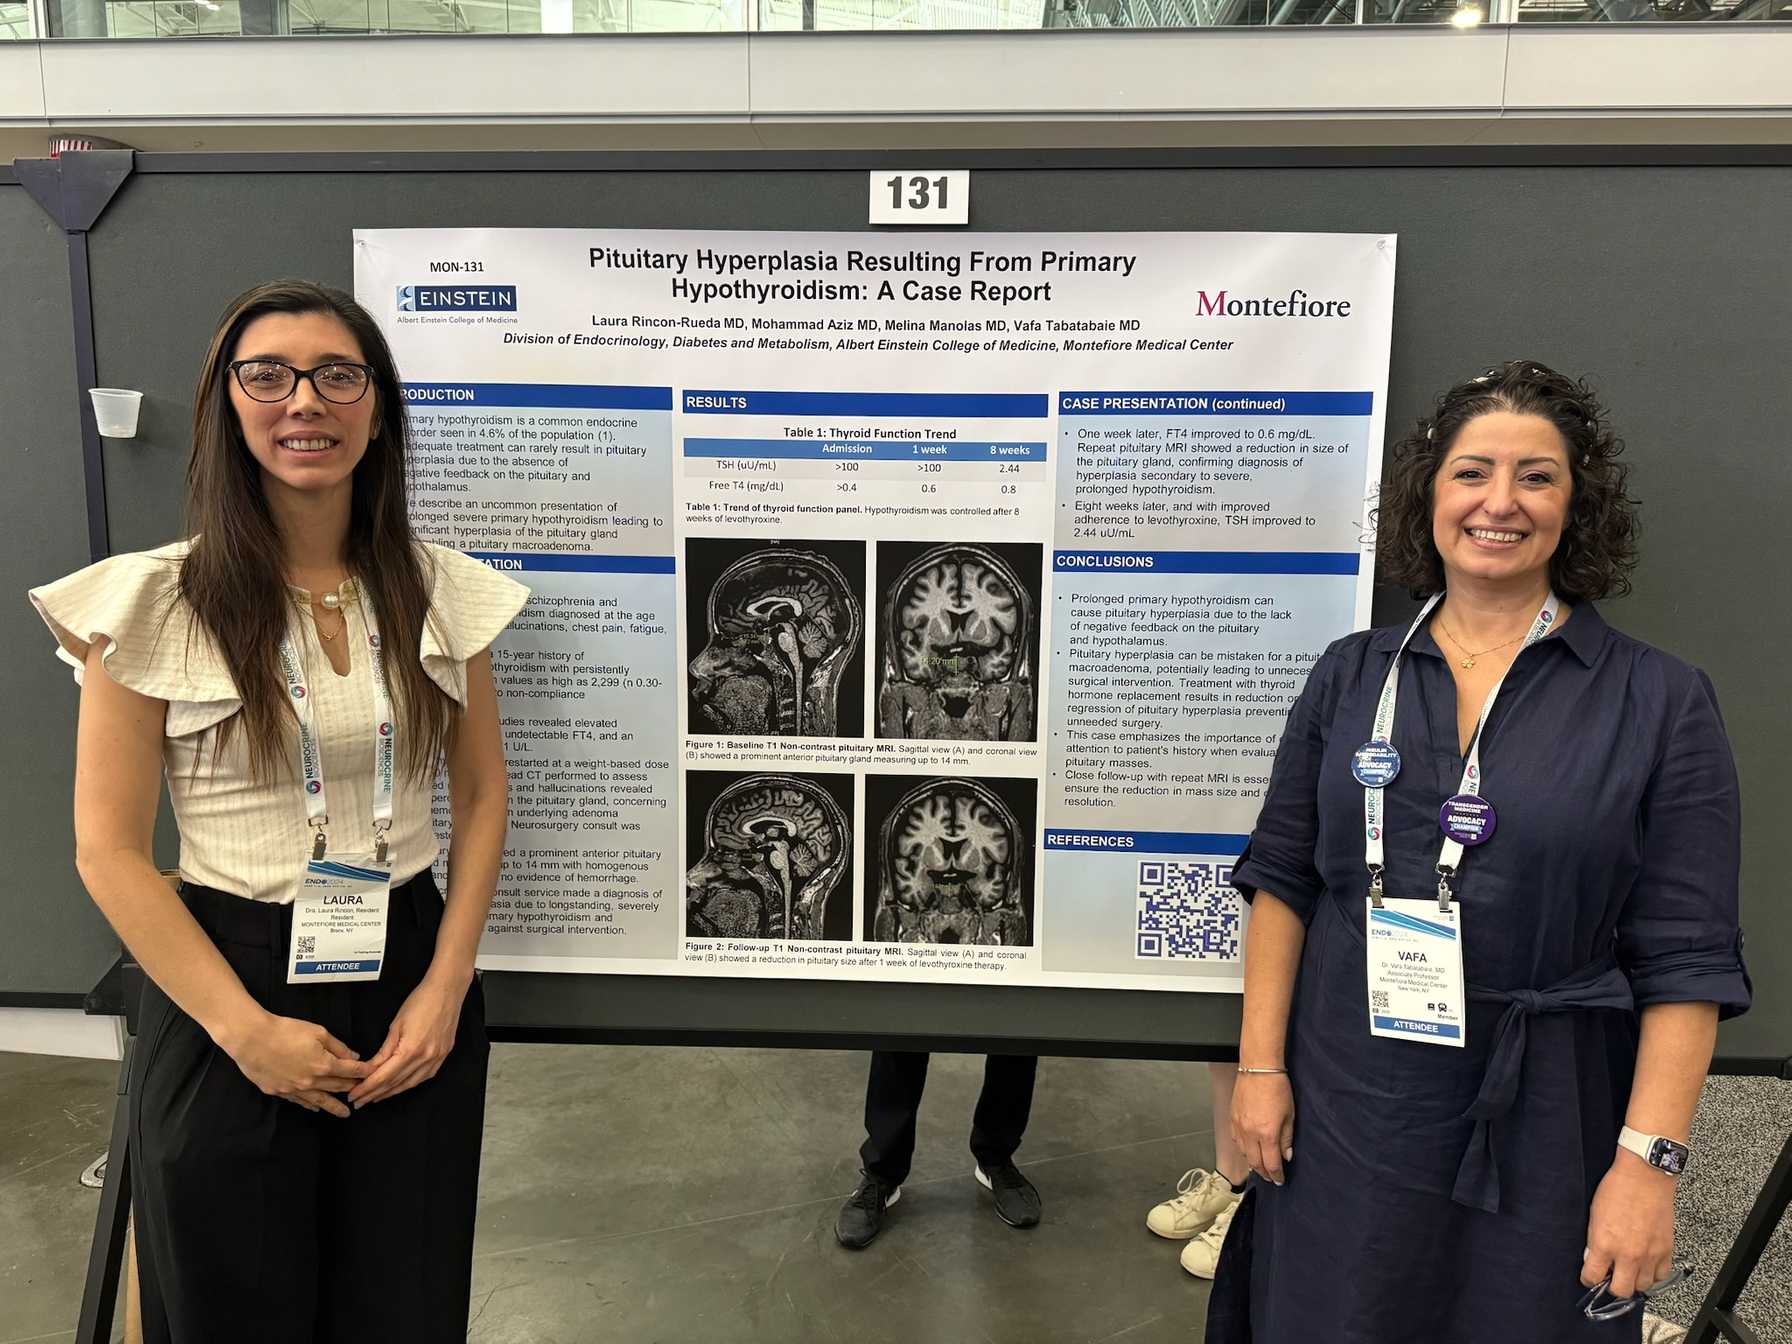

- Multidisciplinary management of complex thyroid, pituitary and neuroendocrine tumors

- Contribution to medical literature through the preparation of case reports, abstracts, posters and manuscripts to present in local, regional and national conferences and forums

Offering rich opportunities for research

Endocrinology Fellows become familiar with research in their first year under the stewardship of Sofiya Milman, MD, Associate Program Director for Research. Depending on their experience and future career interests, fellows can choose to initiate their own research project or join an ongoing project, working with helpful and experienced mentors. Fellows also participate in didactic seminars on research methodology, scientific writing and quality improvement studies. During their training, fellows gain valuable research experience, and most contribute to their field by presenting their findings at regional or national conferences or in a manuscript.